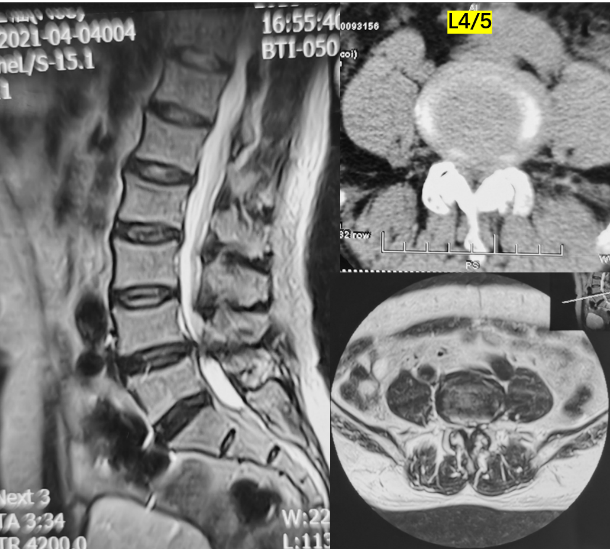

第一例患者女性,73岁,因“腰部反复疼痛20余年,加重伴左下肢疼痛4月”以“腰椎滑脱症(L3、 I°)、腰椎管狭窄症”住院。入院后经术前讨论、评估后制定治疗方案,并与患者及其家属充分沟通,行OLIF手术。术后第二天,患者下地活动,腰痛和左下肢疼痛完全消失,无明显不适,疗效满意。

术前影像

术中